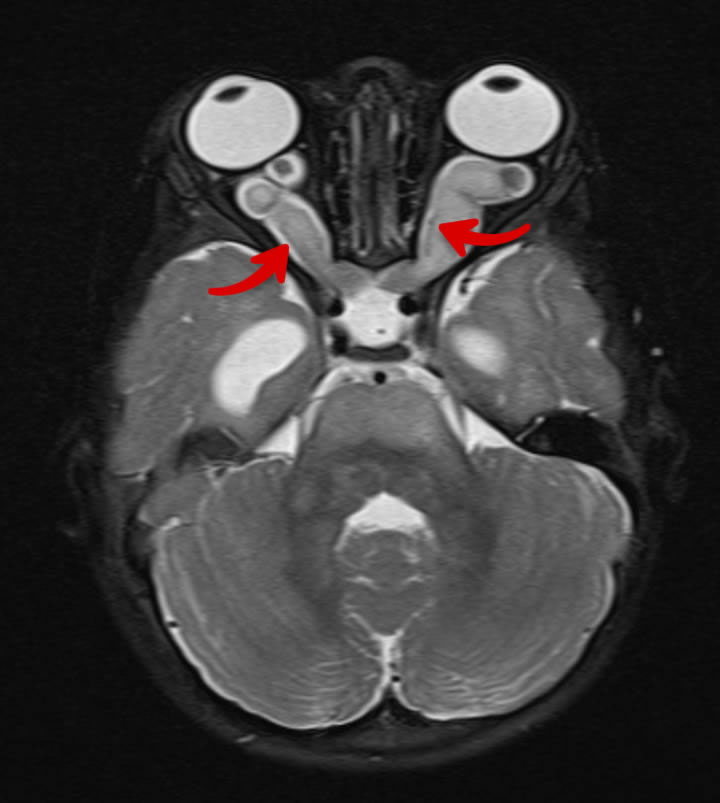

Les gliomes des voies optiques sont des tumeurs touchant les nerfs des yeux. Ce sont des astrocytomes pilocytaires de grade 1, c’est-à-dire d’évolution habituellement lente et qui ne compromettent pas la survie du patient. Ils surviennent principalement entre l’âge de 3 ans et 7 ans et ne sont pratiquement jamais vus chez les adultes.

On les retrouve chez environ 15% des enfants atteints de NF1, mais près de la moitié ne présenteront jamais de symptômes. Lorsqu’ils sont symptomatiques, ces gliomes se manifestent habituellement par une diminution de la vision, et les patients peuvent également avoir des céphalées (maux de tête), une proptose (œil plus avancé), une limitation dans le mouvement des yeux, une puberté précoce ou un retard de croissance.